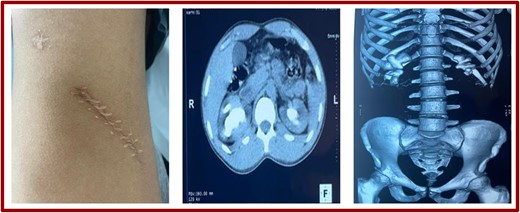

This 27-year-old patient, who had undergone lumbotomy surgery for renal lithiasis 10 years previously, presented to a urology consultation with bilateral low-back pain associated with emission of stone fragments during micturition, which had been evolving for 2 months. This low-back pain was not associated with fever or other lower urinary tract signs. Examination revealed a patient in very good general condition, with a body mass index of 20. A right lumbotomy scar was present (Fig. 1), and there was mild lumbar pain on palpation and percussion.

Lumbotomy scar and scans (coronal sections and reconstruction).

Biologically, hemoglobin was 12 mg/l and plasma creatinine 17 g/dl. Hemostasis was unremarkable. An injection-free abdominopelvic CT scan revealed normal-sized, regularly contoured, well-differentiated kidneys, secreting and excreting within normal timeframes. Coralliform calculi were found in two kidneys measuring 6 cm on the right and 4 cm on the left, with a density of 631 HU on the right and 728 HU on the left (Fig. 1).